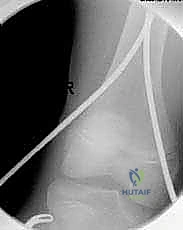

الخطوة الأولى: التجهيز وجهاز الأشعة المرئية (C-Arm)

يتم وضع الطفل على طاولة العمليات الخاصة بشد العظام. يتم استخدام جهاز الأشعة السينية المرئية (C-Arm) الذي يتيح للدكتور هطيف رؤية العظم من الداخل مباشرة على الشاشة أثناء الجراحة، مما يضمن دقة العمل دون الحاجة لفتح الجلد. يقوم الجراح أولاً بـ "رد الكسر" (إعادة العظام إلى استقامتها الطبيعية) باستخدام الشد الخارجي.

الخطوة الرابعة: القص والإغلاق

بعد التأكد من استقامة العظم وثبات الكسر عبر جهاز الأشعة، يقوم الدكتور هطيف بقص الأجزاء الزائدة من المسامير البارزة خارج العظم، مع ترك جزء صغير جداً تحت الجلد لتسهيل عملية إزالتها في المستقبل. أخيراً، يتم إغلاق الشقوق الجراحية الصغيرة بخيوط تجميلية، ووضع ضمادات خفيفة. لا حاجة لأي جبس خارجي!